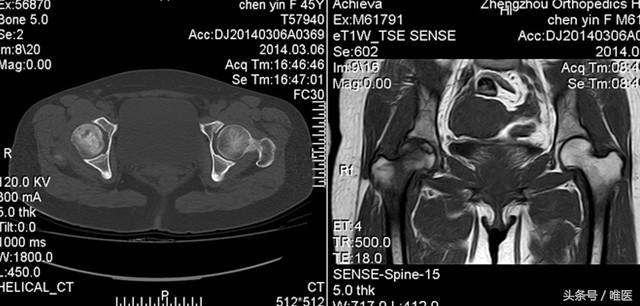

2、影像學檢查:醫(yī)生可能會通過X光、MRI等影像學檢查手段來確診股骨頭壞死。